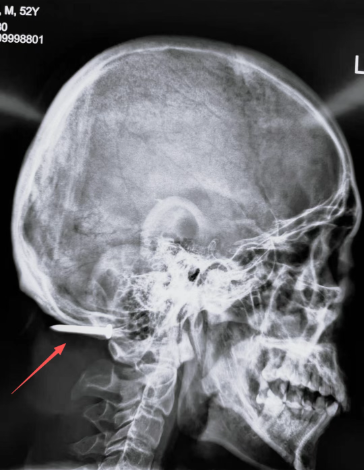

2025年11月12日中午1点,急促的救护车鸣笛声打破了北京积水潭医院回龙观院区的宁静。一名52岁男性患者被紧急送进急诊抢救室,一枚水泥钢钉从的他面部射入,贯穿颅颈部位,生命危在旦夕。

经急诊医师问诊得知,患者是一名工人,作业时不慎被射钉枪击中。射钉枪常用于钢筋混凝土施工,枪口动能巨大,导致钢钉从其左侧下颌射入,先后穿透下颌骨、口腔、颈椎间隙,最终深嵌枕部颅骨下方。伤后患者随即出现呕血症状,虽辗转多家医院,却因病情复杂、手术风险极高,最终被转至北京积水潭医院。

患者术前影像(红色箭头为钢钉位置)

“患者不仅存在贯穿伤,还可能伴随血管、神经及脊柱的严重损伤,必须立即启动多学科协作(MDT)机制。”急诊科主任田兆兴第一时间做出判断,在为患者紧急完善头颅CT、血管造影等检查的同时,组织普外科、血管外科、神经外科、脊柱外科、心脏大血管外科、急诊内科、急诊科创伤重症监护病房(TICU)等多学科讨论诊治方案。

检查结果进一步印证了病情的复杂性。钢钉已击碎患者高位颈椎横突,造成粉碎性骨折,更致命的是左侧椎动脉已完全断裂。“一旦术中血管破损处大出血,后果不堪设想。”经过各科室专家反复研讨、权衡利弊,最终确定了由普外科负责核心手术操作,血管外科、神经外科、脊柱外科同台保障,TICU团队给予术后支持的治疗方案。